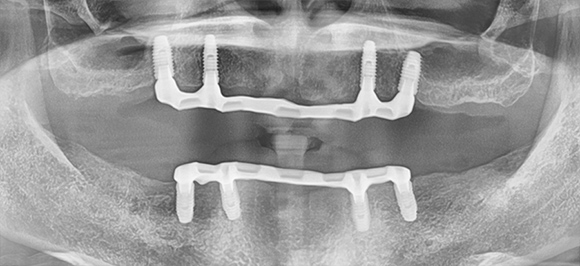

임플란트 틀니

임플란트의 장점인 튼튼한 고정력과 유지력을

잇몸 전체를 덮는 틀니와 결합하여

단일 틀니 사용으로 생길 수 있는 불편함을 개선